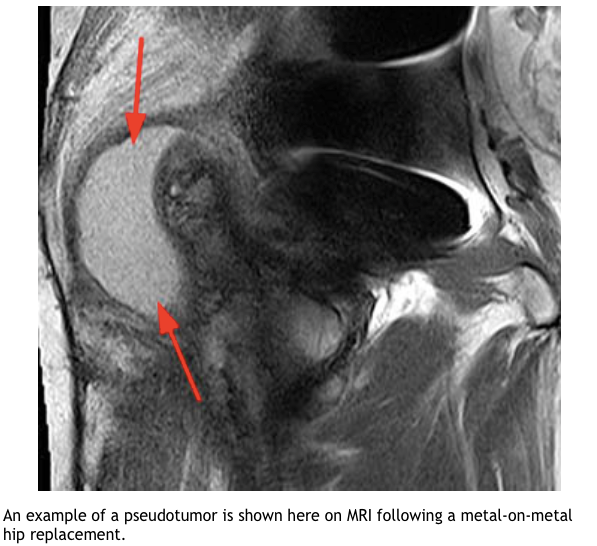

What are the benefits/disadvantages of metal on metal bearing surface?

What are the CI for MOM implants?